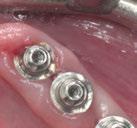

(Figuras 22 y 23). Se realiza fresado transgingival mínimamente invasivo y guiado hasta la inserción de los implantes, siguiendo el protocolo preestablecido e indicado (Figuras 24 a 26).

Durante la colocación de los implantes comprobamos una inserción con torque superior a 35 N/cm2

Retiramos la férula y comprobamos una correcta estabilidad primaria mediante mediación de valores

ISQ favorables en la mayoría de los implantes. Seguidamente se extraen los dientes remanentes que han actuado de medio retentivo para la férula quirúrgica.

Dentro de la fase quirúrgica propiamente dicha, una vez terminada la inserción de los implantes y

comprobada su estabilidad primaria, colocamos pilares transepiteliales

Multiplus para registrar una impresión digital mediante escaneado sobre ellos (Figuras 27 a 29)

Dado que la estabilidad primaria se ha conseguido en la mayoría de los implantes, coincidiendo con la previsión propuesta en la planificación, procedemos ahora a la fase protésica. En el caso que nos ocupa, la paciente reside lejos, por lo tanto, colocamos tapones sobre los pilares transepiteliales y descansa en la sala de recuperación (Figura 30).

aproximadamente una hora y media. Usamos resina Bego VarseoSmile TriniQ® para puentes definitivos. Aunque en este caso la vamos a usar para confeccionar unas prótesis fijas atornilladas provisionales de larga duración, dado al aumento de dimensión vertical que vamos a realizar a la paciente, de esta forma obtendremos una neuroprogramación de la ATM reinstaurando una Dimensión Vertical apropiada y mejorando la estética facial de la paciente. Excluimos de la carga aquellos implantes que no obtuvieron una estabilidad primaria superior a 35 N/ cm2. El material permite la realización de una carga inmediata en material definitivo en puentes (Figuras 31 a 38).